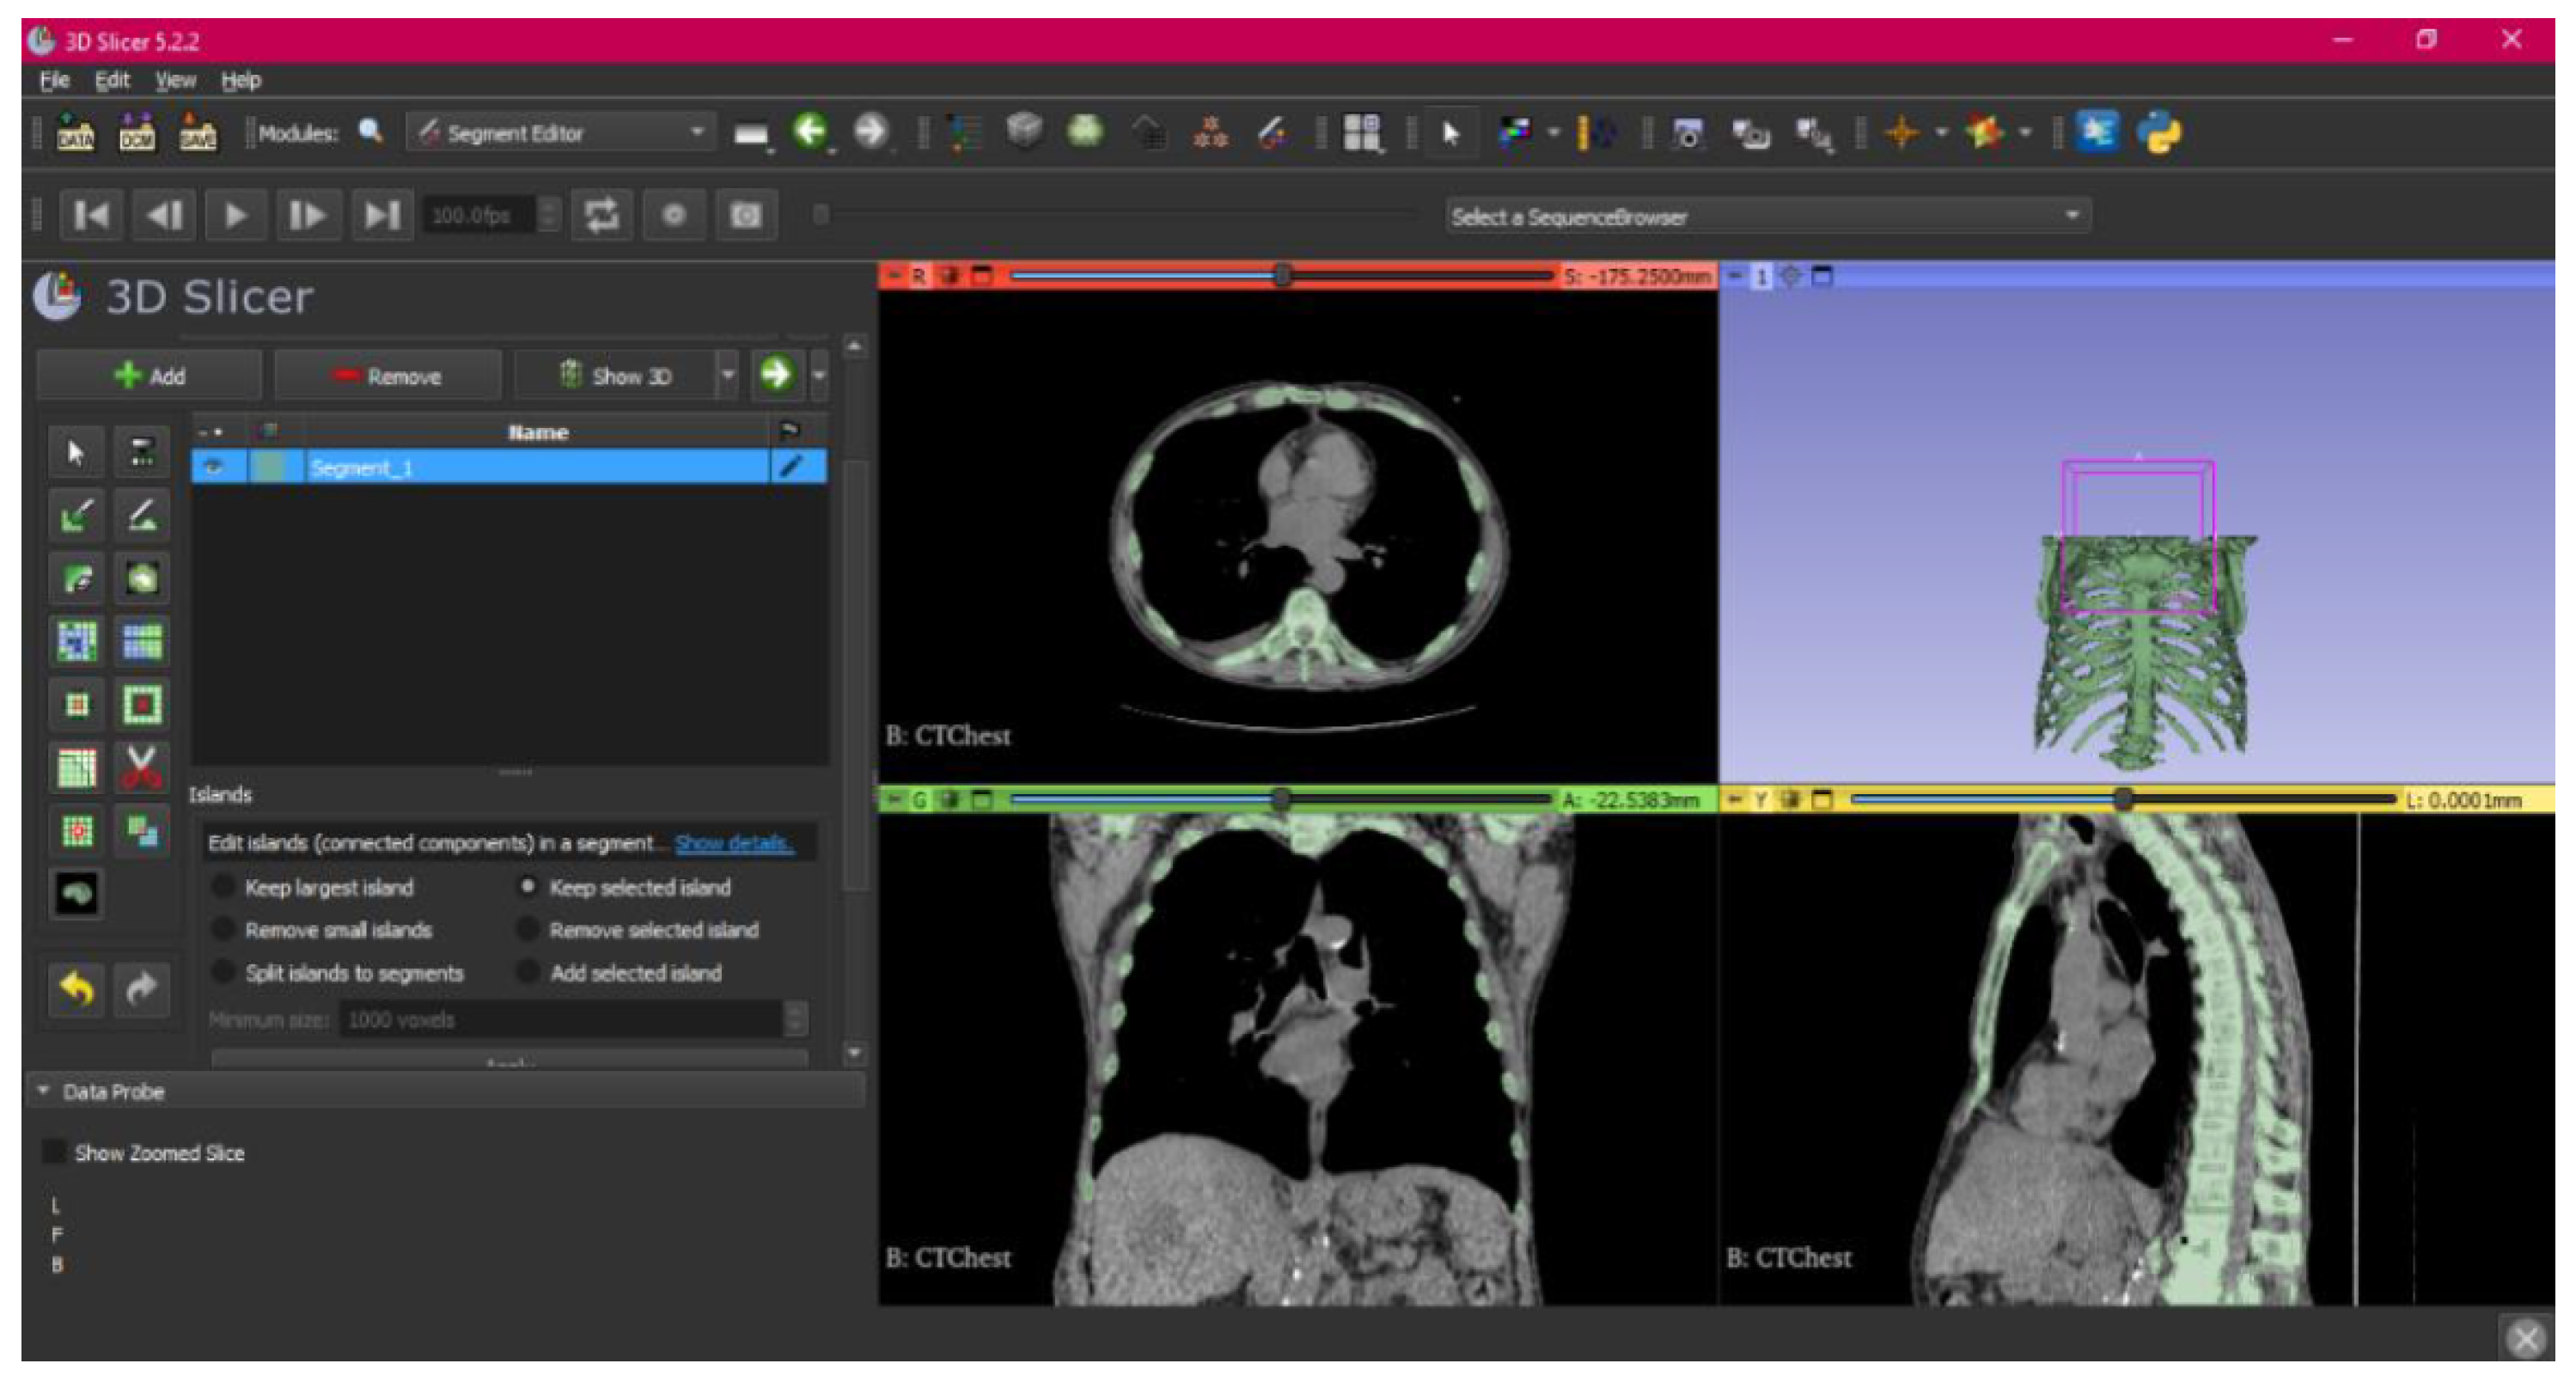

- Use the “Islands” tool.

- Select the “Keep selected islands” option, and mark the areas of interest in one of the views.

- Select the “Scissors” tool.

- Configure the options “Erase inside”, “Free-form’,’ and “Unlimited”.

- In the views, select and delete unwanted parts until the desired anatomical structure is obtained.